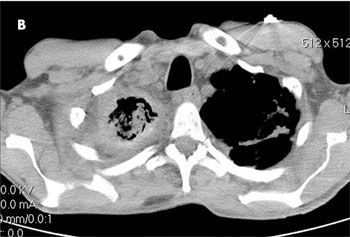

The patient was afebrile. Oxygen saturation was 99% on room air. Positive findings were dry inspiratory crackles and rhonchi in the right lung field, and a mobile, 1 x 1-cm, mildly tender right cervical lymph node. A chest radiograph revealed right apical pleural thickening involving the upper half of the right hemithorax, cavitation with an air-fluid level, emphysematous bullae, and scarring in the left upper lung (A). A CT scan of the chest showed a complex 7.6 x 6.2-cm cavity with thick and irregular walls in the right lung with volume loss and scarring (B and C). An extensive amount of heterogeneous material was located within the cavity. Scarring and bronchiectasis in the left upper lung and multiple lymph nodes (the largest, 2 x 2 cm) in the right hilum were also noted.